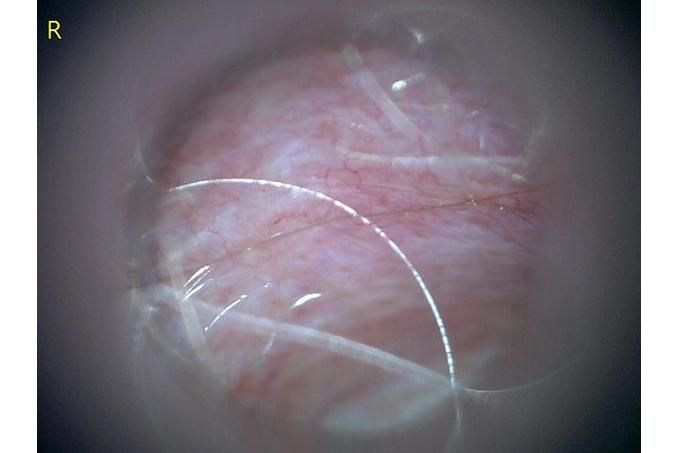

사진만 보고 확진할 수는 없지만 지금 올려주신 귀는 적어도 오른쪽은 정상으로 보이기 어렵습니다 왼쪽은 비교적 연분홍에 가까워 보이지만 오른쪽은 털과 분비물이 많이 차 있고 피부가 자극받은 듯한 모습이라 외이염 가능성을 먼저 생각하게 됩니다 그리고 질문자님이 적어주신 머리 털기 하루 여러 번 귀 만질 때 통증 솜만 닿아도 예민함 귀 긁기 같은 증상은 외이염에서 흔한 신호입니다

지금 제일 조심해야 할 것은 귀세정을 무조건 하는 것도 무조건 안 하는 것도 아니라는 점입니다 고막 상태를 확실히 모르는 귀에 자극적인 세정제를 넣거나 세게 세정하면 더 아프고 더 깊은 쪽을 자극할 수 있습니다 특히 알코올 성분 세정제는 염증 있는 귀에서 따갑고 자극적일 수 있고 고막이 손상돼 있으면 더 문제가 될 수 있습니다 그래서 지금처럼 오른쪽이 아픈 귀는 집에서 강하게 세정하는 쪽은 저는 말리고 싶습니다